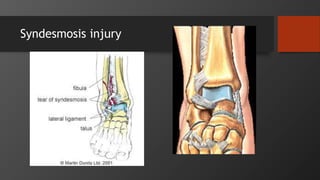

Syndesmosis injury